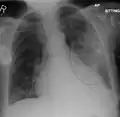

The discovery of x-rays made it possible to determine the anatomic type of pneumonia without direct examination of the lungs at autopsy and led to the development of a radiological classification. Early investigators distinguished between typical lobar pneumonia and atypical (e.g. Chlamydophila) or viral pneumonia using the location, distribution, and appearance of the opacities they saw on chest x-rays. Certain x-ray findings can be used to help predict the course of illness, although it is not possible to clearly determine the microbiologic cause of a pneumonia with x-rays alone.